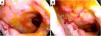

La colonoscopia mostró una mucosa rectal friable con erosiones y una úlcera en el canal anal, lo que evidencia una proctitis infecciosa (fig. 1). Inicialmente, se consideró la proctitis de origen infeccioso, incluyendo infecciones bacterianas (como Treponema pallidum, Haemophilus ducreyi, Chlamydia trachomatis, micobacterias), virales (citomegalovirus o herpes simple) u hongos (como C. neoformans). La histopatología de las biopsias rectales identificó la presencia de levaduras de C. neoformans, confirmando el diagnóstico (fig. 2).